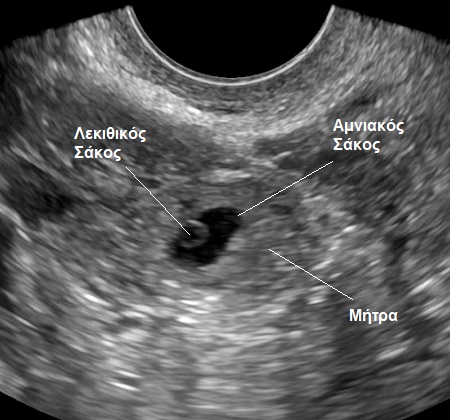

Η πρώτη ανατομική δομή του εμβρύου, που εντοπίζουμε υπό κανονικές συνθήκες εντός του αμνιακού σάκου είναι ο λεκιθικός σάκος (ή «ασκός»).

Πρόκειται για ένα μικρό σφαιρικό όργανο, το οποίο στο υπερηχογράφημα απεικονίζεται ως ένας μικρός κύκλος μέσα σε έναν μεγαλύτερο κύκλο, που είναι ο αμνιακός σάκος (βλ. εικόνα).

Τότε ο σάκος θα φανεί σαν ένας μικρός μαύρος κύκλος μέσα στη μήτρα σας (βλ. εικόνα).

Ο σάκος αυτός είναι αρχικά μικροσκοπικός, στη συνέχει αναπτύσσεται, ώστε να καταλάβει ολόκληρη την ενδομητρική κοιλότητα. Το μέγεθος του σάκου ακολουθεί το μέγεθος του ραγδαίως αναπτυσσόμενου μωρού και του πλακούντα και πιέζει τα όρια της ενδομητρικής κοιλότητας (βλ. εικόνα). Έτσι και η μήτρα διογκώνεται σταδιακά με το βάρος της στο τέλος της κύησης να υπερβαίνει το ένα κιλό από το αρχικό βάρος των περίπου 100 γραμμαρίων της μη εγκυμόνου μήτρας.